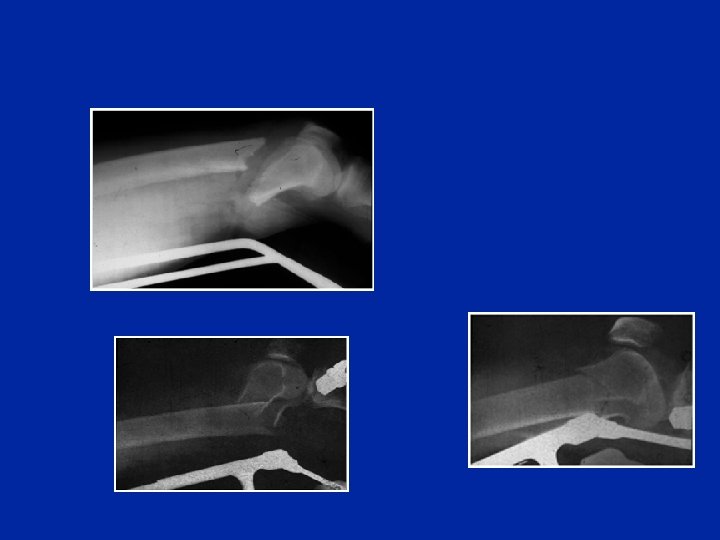

Fratture monocondiliche di Hoffa

Distacchi epifisari

n Trauma in iper-estensione del ginocchio n Salter 1 n Nessun trauma vascolare ma disestesie del dorso del piede n Rischi cutanei alla faccia postesterna del ginocchio 12 anni